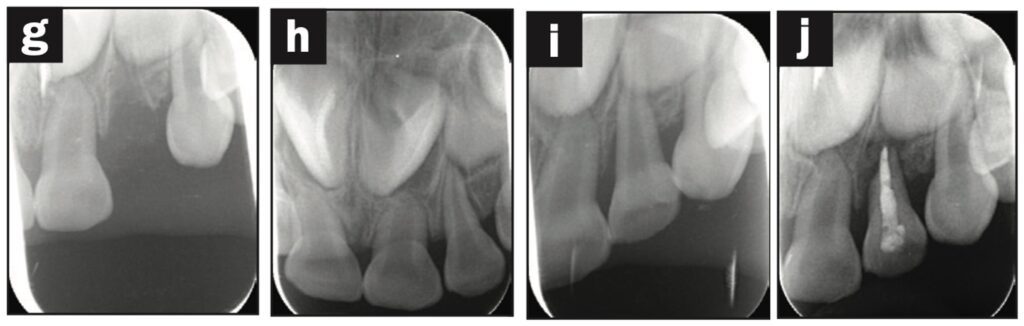

Bệnh nhân là một bé gái 5 tuổi bị ngã đè lên chai nước khi đang uống nước và bị bật răng cửa sữa bên trái ra ngoài. Nhân viên chăm sóc trẻ đã rửa răng bằng nước máy và làm sạch chất bẩn trên răng, loại bỏ màng nha chu.

Răng được đặt lại và cố định bằng composite quang trùng hợp, sau đó lấy dấu. Bệnh nhân quay lại phòng khám nha khoa 3 tiếng sau đó và nhận khay duy trì.

Dặn dò phụ huynh để cho bệnh nhân phải đeo hàm duy trì cả ngày trừ lúc đánh răng. Răng được kiểm tra sau 1, 7, 14 và 21 ngày và chụp X quang sau 28 ngày. Điều trị nội nha được thực hiện sau khi răng đã ổn định.

Quá trình theo dõi 12 tháng trong giới hạn bình thường (hình 1f).